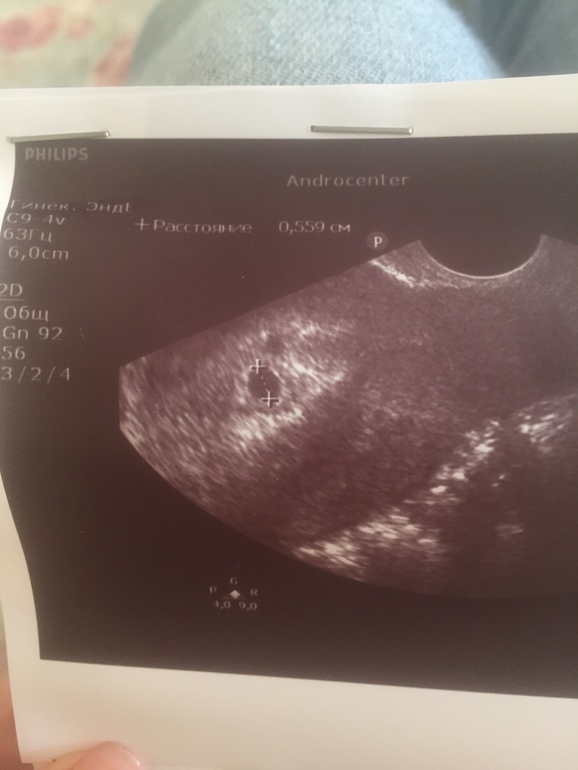

Узи понедельник

Только что вернулась с узи. Врач больше часа смотрела на аппарате. Я сразу не говорила что мне поставили ПЗ под вопросом два дня назад. Но почти сразу врач стала очень насторожена и тщательно рассматривала. Ее мнение - пришла я очень рано и что то конкретное глвлрить сложно. Плодное яйцо есть, но рядом есть еще что-то. На ее аппарате назвать структуру множественной нельзя. На второе плодное ни по форме ни по контуру не похоже. Желтое тело одно в правом яичнике. Левый вообще прижат к матке (возможно спайки). На кисту или отслойку не похоже (нет гематомы). Я потом уже сказада что это второе узи на другом аппарате. Врач внимательно рассматривала чтоб исключить Пузырный, но говорит что он выглядит по другому но есть вероятность что просто рано и он еще может развиться. поставила тоже пузырный под вопросом.